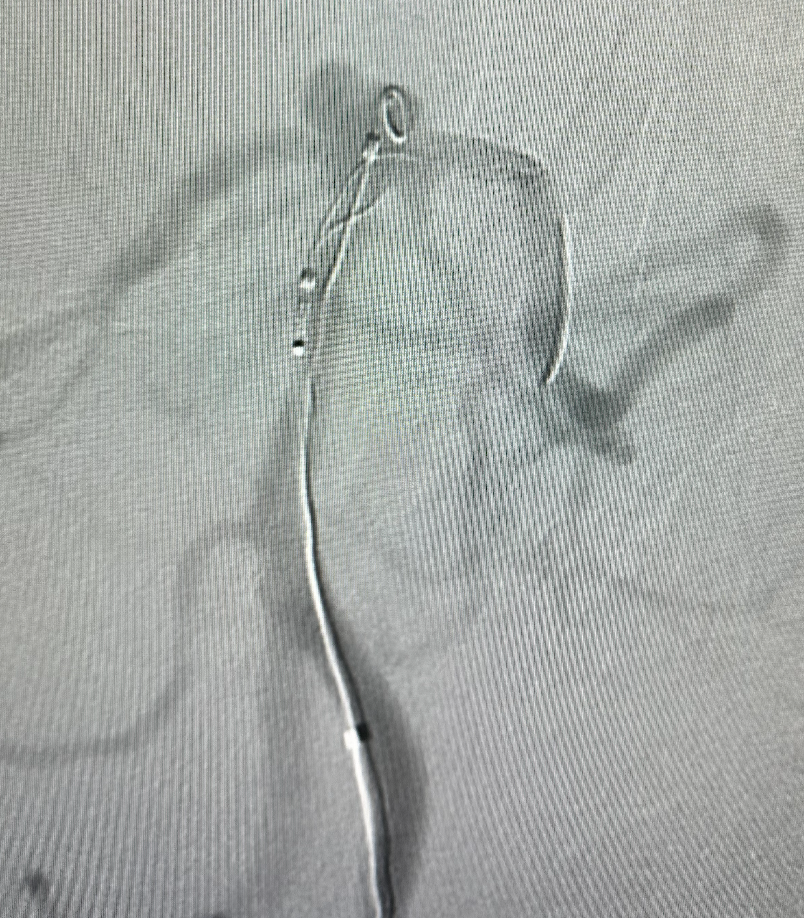

继续释放并调整 畅医达(TaminoVIA)颅内动脉瘤辅助栓塞支架 至合适位置,支架两端为闭环设计,操作过程中能减少血管壁损伤,瘤颈处部分推密增加金属覆盖率

畅医达(TaminoVIA)颅内动脉瘤辅助栓塞支架完全释放,打开效果好,显影清晰,瘤体部分显影

畅医达(TaminoVIA)颅内动脉瘤辅助栓塞支架两端为闭环设计,能减少血管壁损伤、同时增强支架整体径向支撑力;且支架系统通过性好,输送难度低,打开效果好显影清晰,释放操作简单。‍